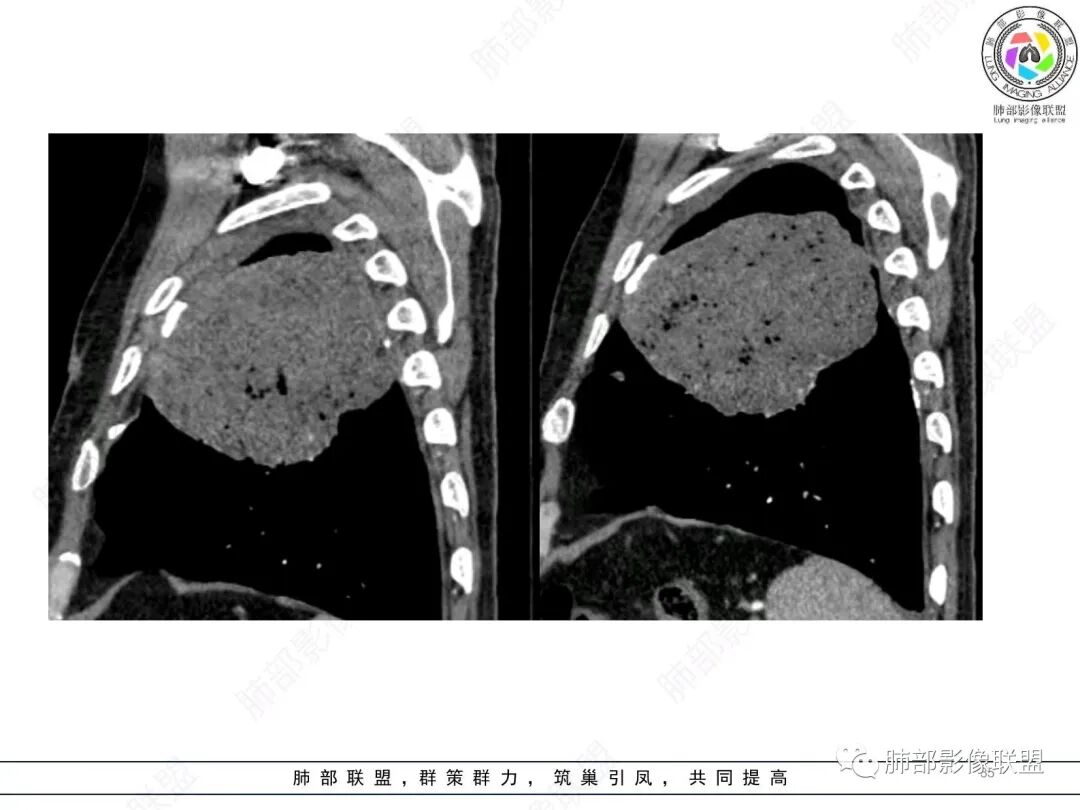

大肿块,边缘光滑,深分叶

近端支气管堵塞、推移为主

部分类似于脐凹征

内部支气管扩张

肺动脉推移为主,边缘部分进入

大肿块、表面光滑但深分叶,肺门侧支气管堵塞

回头看,内部支气管近端其实不连续,伴随肺动脉不存在

这两点就不符合

1)部位:周围型或中央型软组织肿块,以周围型为多见,且肿瘤多位于肺上叶。如本例:该肿瘤位于左肺上叶。

2)大小及形态:由于本病恶性程度高,早期症状不明显,发现时肿块均较大。如本例病变巨大。

3)肿块边界和边缘:多较清楚,呈圆形、类圆形,且由于肿块生长速度不均匀,可见分叶,毛刺少见。有报道肿块周围毛玻璃影是多形性癌特征表现。

4)密度:肿块平扫为软组织密度,由于体积较大,内部常见大片状坏死,可出现不规则厚壁空洞或坏死内多发无壁小空洞,坏死多不均匀:坏死灶内可见如柳絮样的斑片样强化灶,坏死边缘与非坏死区分界不清本例坏死较明显,密度不均匀。

5)肿瘤强化方式:肺部恶性肿瘤强化程度与其血供丰富程度相关,血供丰富多强化明显,反之则较差。由于PSC 周边实性部分富血供及内部黏液变性、坏死,增强后肿块多数呈轻-中度边缘环形强化或不均匀小斑片状强化。国外学者对照病理发现肿瘤细胞或胶原组织增强扫描时强化,无强化的低密度区代表了黏液样变性区和出血坏死区。